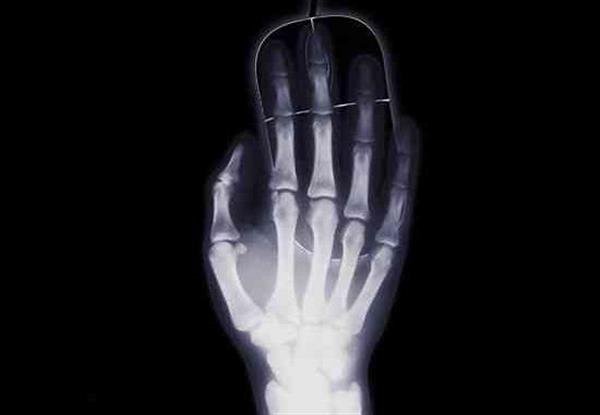

值得注意的是,這種3D打印骨頭的新方法還將使用一種叫做聚羥基丁酸酯(PHB)的可充分生物降解材料。西伯利亞聯(lián)邦大學(xué)(SFU)生物科學(xué)博士Catherine Shishatskiy解釋說,3D打印技術(shù)讓他們在設(shè)計和制作骨骼方面獲得了巨大的自由。此外,由于斷層照影技術(shù),比如CT和核磁共振等,的使用,其3D模型的精度可以達(dá)到前所未有的水平。不可否認(rèn),掃描和3D打印技術(shù)的組合為自定義設(shè)計解剖植入物,比如3D打印骨骼,打開了大門。

參與該項目的另一位研究人員Constantine Kisterskiy還指出,通過將這種可生物兼容的材料用于骨骼的增材制造,即將該材料有效地一層層融合在一起,他們還消除了對一定化學(xué)結(jié)構(gòu)和膠粘劑的需求。據(jù)e鍵打印了解,這種3D打印材料是俄羅斯Krasnoyarsk地區(qū)的科學(xué)家在以前的研究項目基礎(chǔ)上開發(fā)出來的。根據(jù)俄羅斯媒體的報道,SFU的一位醫(yī)學(xué)博士Ekaterina Shishatskaya曾經(jīng)因為此類材料的研究在2010年獲獎。